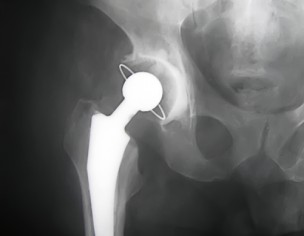

can you tell if its 9 days or 9months? then i can give Some advice. do you have any other xrays?show them as well

Xray you sent me shows total hip replacement, if she still got pain then better to contact the surgeon who has operated to rule out infection or other technical problems which he probably faced during surgery. However You are welcome to see me in Islamabad.

From the Xray it appears the implant has loosened.